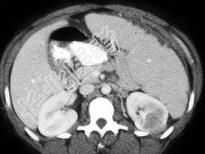

- 单项选择题患者有镰刀形红细胞特征,结合图像, 最可能的诊断为 ( )

A、脾梗死

B、脾脓肿

C、脾出血

D、脾隔离症

E、以上都不是